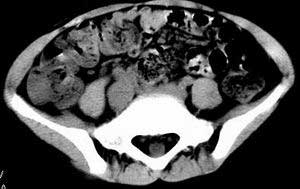

| 患者,男,9岁,因右下腹包块入院,血象不高,不规则发热,常超40度。 平扫: ![]() ![]() ![]() ![]() ![]() ![]() ![]() ![]() ![]() ![]() ![]() ![]() ![]() ![]() ![]() ![]() ![]() ![]() 增强: ![]() ![]() ![]() ![]() ![]() ![]() ![]() ![]() ![]() ![]() ![]() ![]() ![]() ![]() jiajie发言:骶椎右前区不规则软组织肿块,边缘光整,密度均匀,增强后均匀强化,右腹股沟区可见肿大淋巴结,临床有时发热,考虑淋巴瘤,儿童盆腔肿瘤应与神经母细胞瘤和横纹肌肉瘤鉴别。 longzhanghui发言:印象:盆腔右后壁不规则软组织肿块,并向前延伸.似为多个肿块融合,呈中等强化.初步考虑淋巴瘤. 听蝉观竹发言:右侧髂内、外组淋巴结肿大,从其形态和融合的情况看,同意大家意见-----考虑恶性病变,但是9岁男孩还要注意检查睾丸情况,有无隐睾? 常常类似情况是隐睾发生精原细胞瘤淋巴结转移,这个病例也要注意这一点!!! 广东凌发言:大家好,在这里我想说一下个人观点,我建议上传图片的同志能否辛苦一点就是把病史和图片都上传完整一点,比如这个病人的腹膜窗,并且这个病人的肠道的准备也是不怎么好,就从现有的质料看:病灶属于淋巴结肿大当无大的争议,有融合趋势,其内无坏死,边缘强化为主,故考虑:淋巴瘤!建议用腹膜窗看一下和肠道的关系! 阿圣发言:病灶属于淋巴结肿大当无大的争议,有融合趋势,其内无坏死,边缘强化为主,故考虑:淋巴瘤 结果是:淋巴瘤 病例来源:ct762。由宁静致远发布: http://www.radinet.com.cn/forum_view.asp?forum_id=4&view_id=2182 |